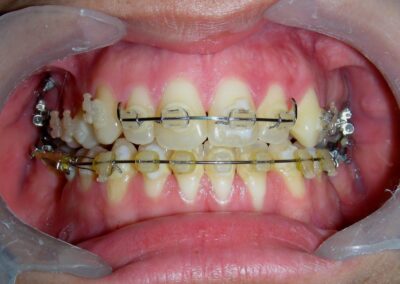

Having successfully achieved the expansion, we proceed to the intrusion of the posterior superior sectors, modifying the Hyrax by adding anchoring hooks at the buccal level of the first premolars. Using the Hyrax as anchorage, we sought a parallel intrusion. This could be replaced by a palatal bar. TADs were installed bilaterally at the mesial level of the first molars, inserting them as parallel as possible to the roots.

Simultaneously we begin with the alignment of the lower arch ,Simultaneously we began with the alignment of the lower arch with Roth prescription ceramic braces .022 . Henry Schein®

As the reader may infer, alignment and leveling of the upper anterior segment are being intentionally deferred at this stage of treatment. This strategic decision is based on the primary objective of closing the anterior open bite not through anterior extrusion, but by means of controlled posterior intrusion. This biomechanical approach promotes a counterclockwise rotation of the mandible, which leads to a increase in the facial axis angle and improvement in vertical facial proportions. By avoiding early anterior alignment, we prevent any premature vertical displacement of the upper incisors.

Clinical changes became evident after 12 months of treatment with posterior intrusion with TADs and nickel-titanium closed coil spring (NiTi), until subsequent follow-up appointments revealed no further significant changes. At that point, it was noted that the most distal molars remained in occlusal contact and had not followed the intrusive movement of their mesial neighbors.